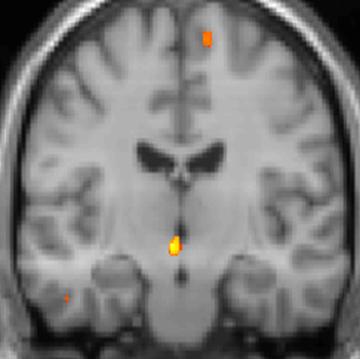

복셀 기반 형태 계측법 이미지 1: 뇌 영역의 구조적 차이

복셀 기반 형태 계측법 이미지 2: 뇌 영역의 구조적 차이

복셀 기반 형태 계측법 이미지 3: 뇌 영역의 구조적 차이

실제로 양전자 방출 단층 촬영술(PET) 스캔 연구 결과, 군발 두통 발작 중에 통증이 없을 때와 비교하여 시상하부의 특정 영역이 활성화되는 것이 관찰되었다. 또한, 복셀 기반 형태 계측법(VBM)을 이용한 연구에서는 군발 두통 환자와 그렇지 않은 사람 사이에 뇌 구조를 비교했을 때, 시상하부의 일부 영역에서 구조적인 차이가 발견되기도 했다.[35] 이러한 영상 연구 결과는 시상하부가 군발 두통의 발생과 관련이 깊다는 가설을 뒷받침한다.